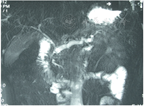

CP典型的CT表现为胰腺钙化、胰管扩张、胰腺萎缩,其诊断的灵敏度和特异度分别为80%、90%以上[24]。CT检查是显示胰腺钙化的最优方法(图2),CT平扫检查可显示胰腺微小钙化灶。常规MRI检查对CP的诊断价值与CT相似,对胰腺实质改变检查敏感,但对钙化和结石的显示不如CT。MRCP主要用于检查胆、胰管的病变,如主胰管扩张、胰腺先天变异、胆管扩张或狭窄等(图3)。